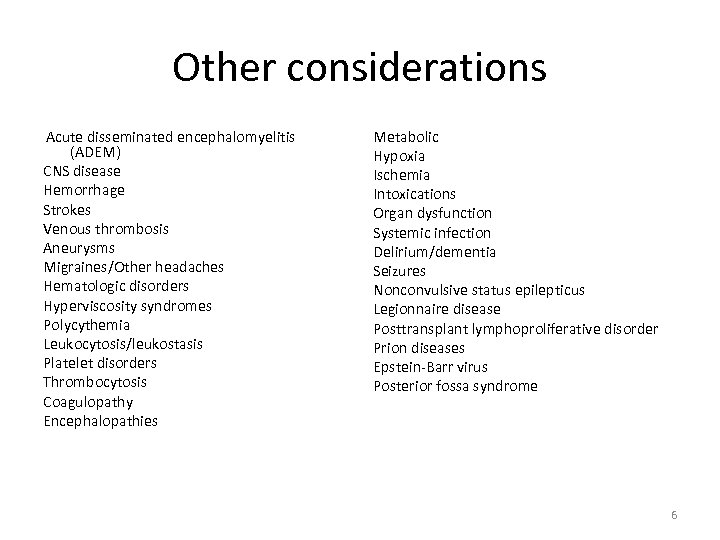

Other considerations Acute disseminated encephalomyelitis (ADEM) CNS disease Hemorrhage Strokes Venous thrombosis Aneurysms Migraines/Other headaches Hematologic disorders Hyperviscosity syndromes Polycythemia Leukocytosis/leukostasis Platelet disorders Thrombocytosis Coagulopathy Encephalopathies Metabolic Hypoxia Ischemia Intoxications Organ dysfunction Systemic infection Delirium/dementia Seizures Nonconvulsive status epilepticus Legionnaire disease Posttransplant lymphoproliferative disorder Prion diseases Epstein-Barr virus Posterior fossa syndrome 6